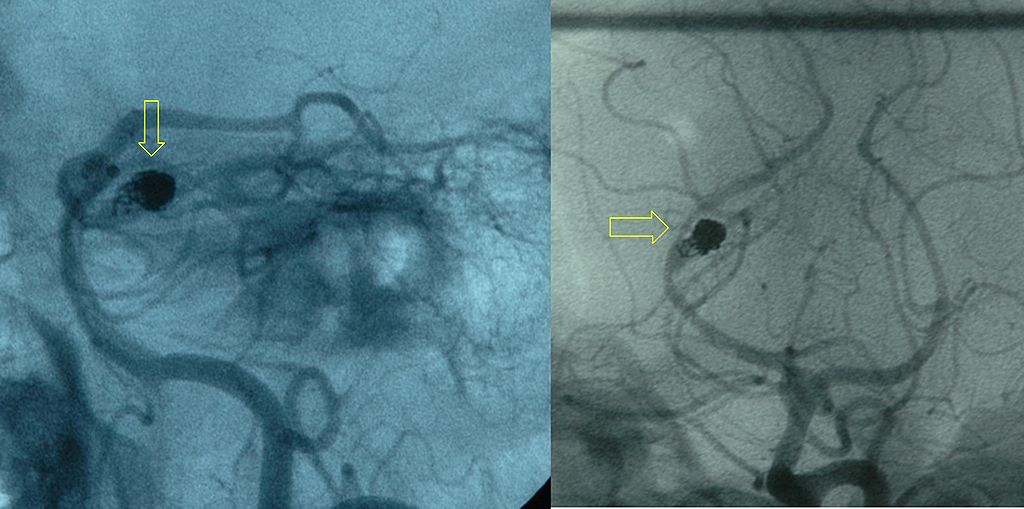

Causes of subarachnoid hemorrhage include:

- Berry aneurysm rupture (85% of cases)

- Arteriovenous (AV) abnormalities